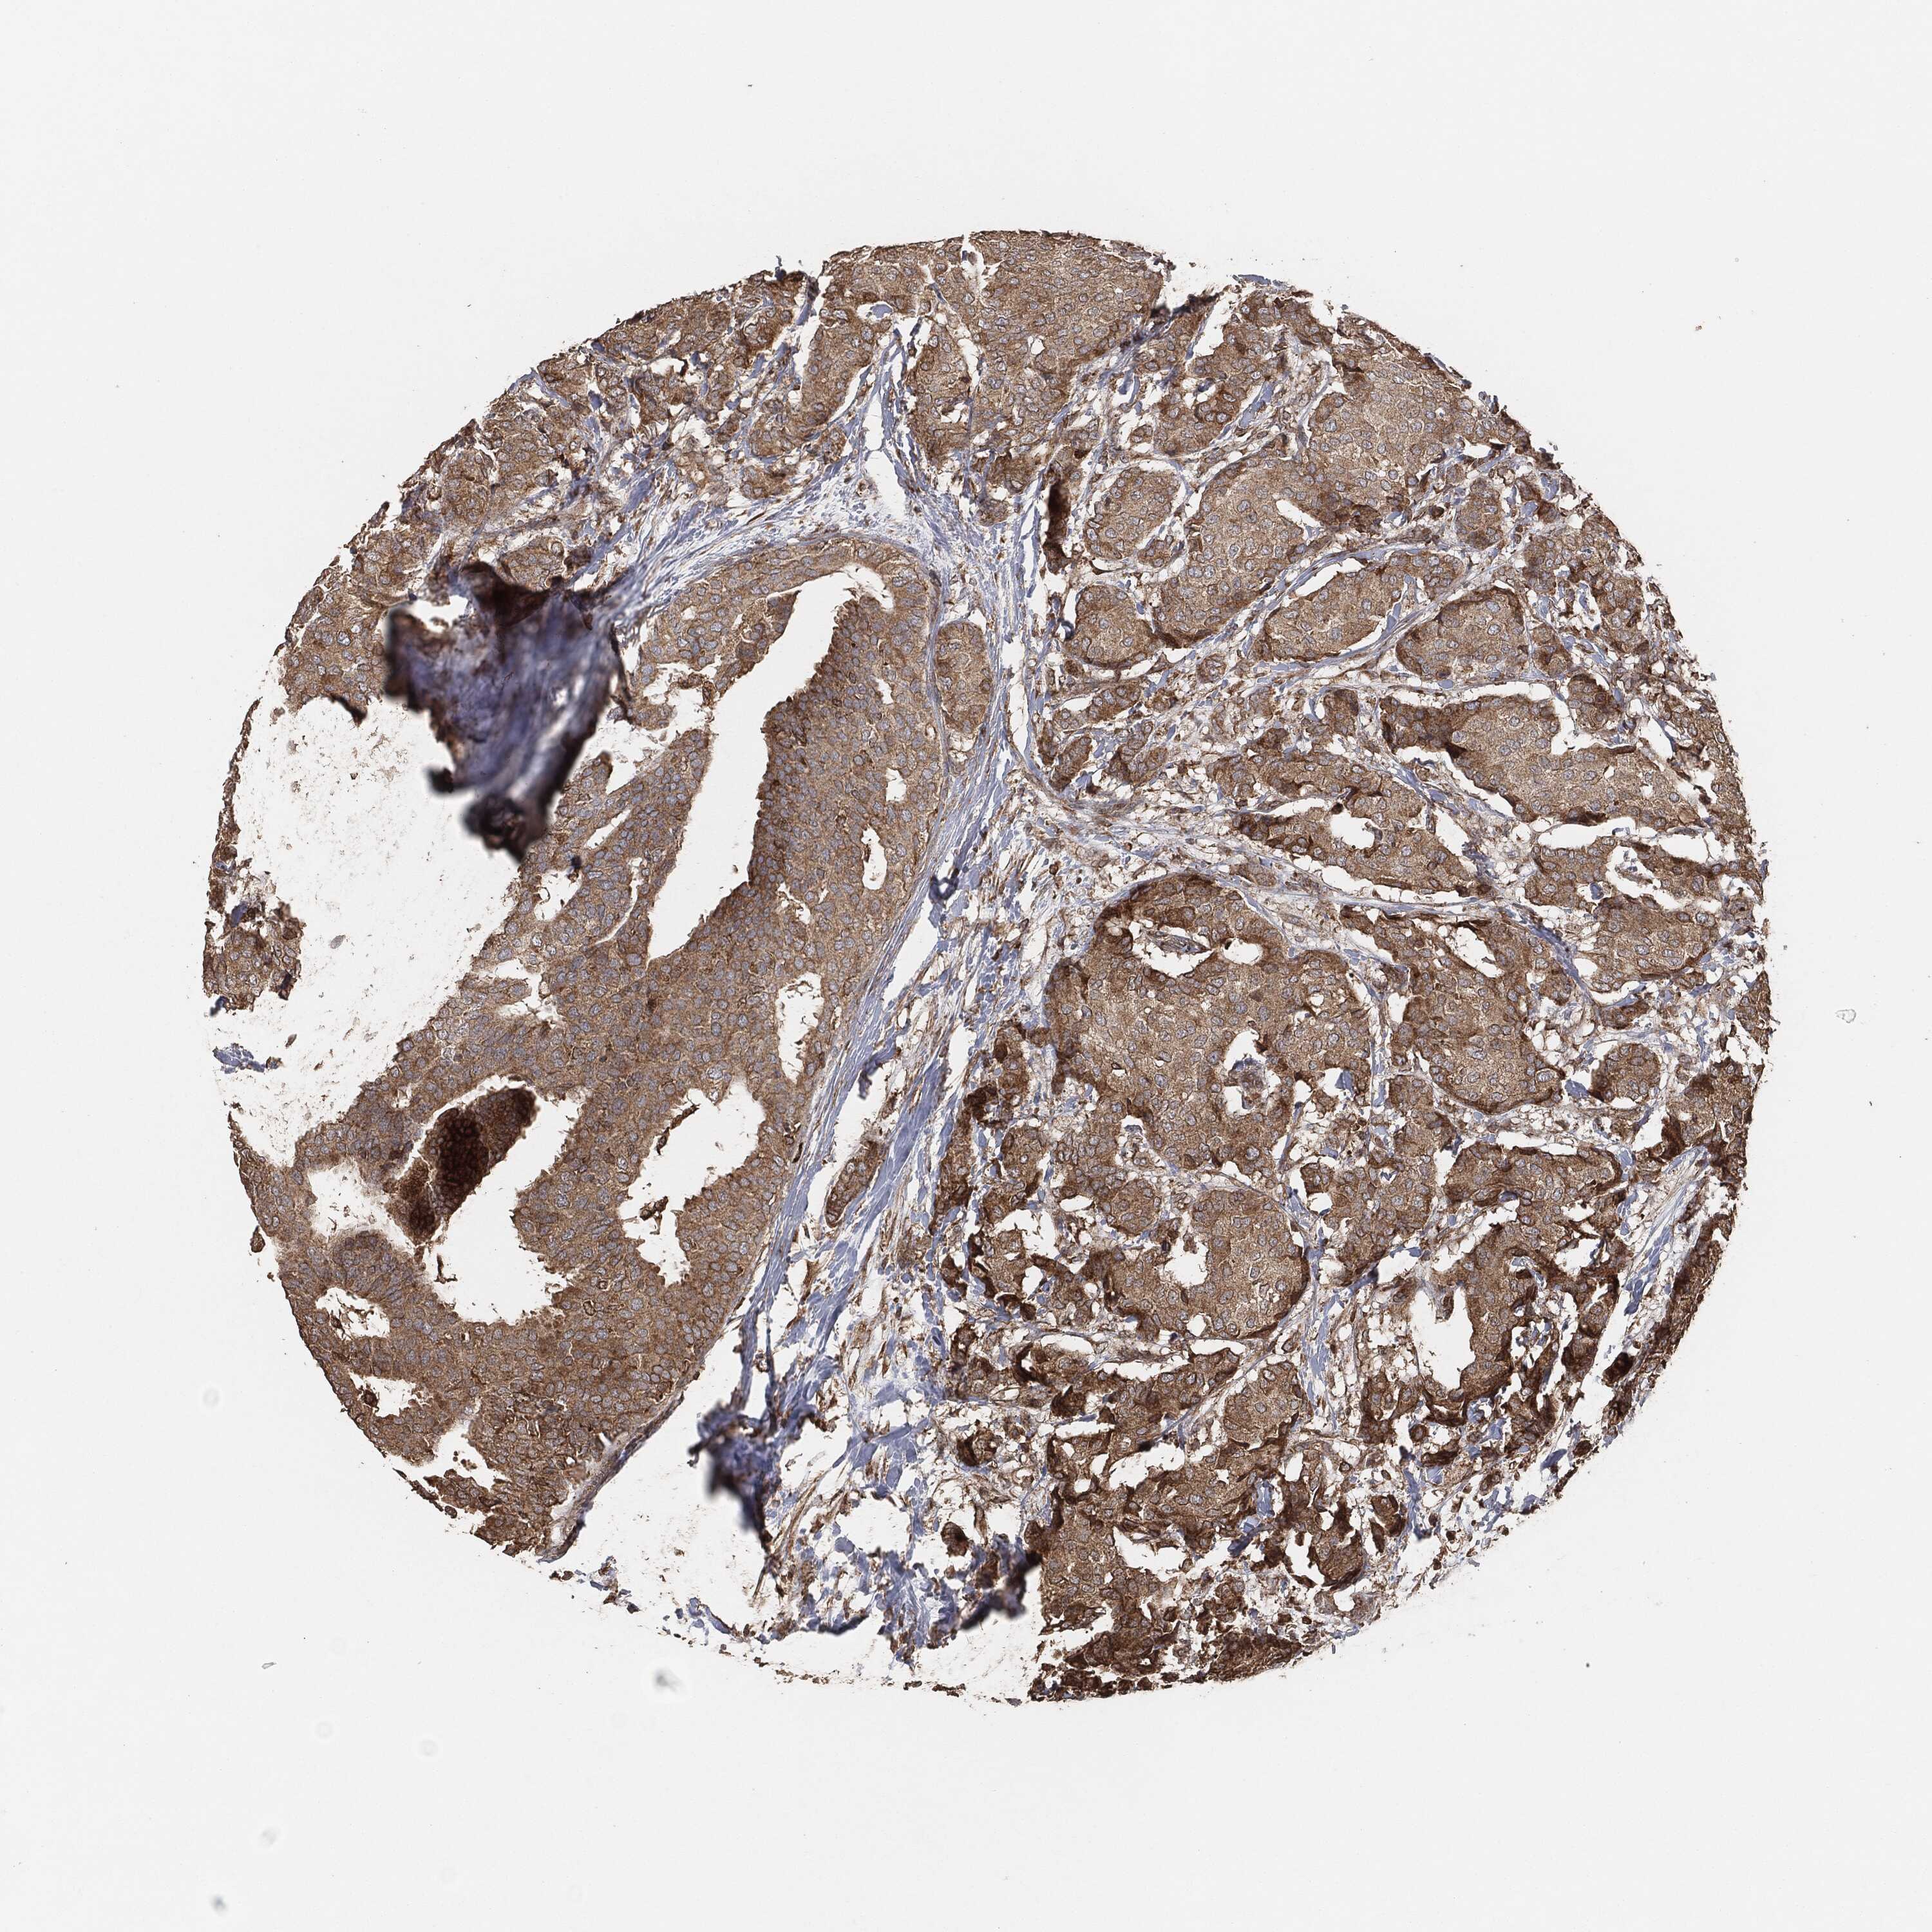

CANCER BREAST CANCER Show tissue menu

BRCA TCGA BRCA VALIDATION PROTEIN EXPRESSION

ANTIBODIES

AND

VALIDATION